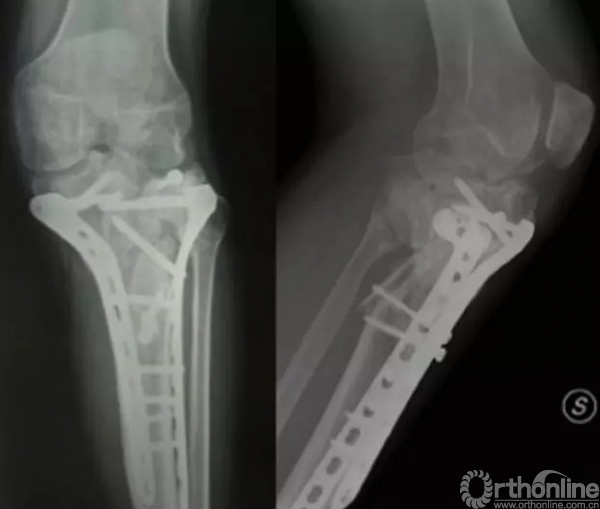

第五,腓骨头是否固定?我们看这个病例。

这是一个简单的IV型骨折,采用内侧支撑钢板固定。

该固定较好的把内侧进行了固定,但是,需要注意在这种情况下,需要检查膝关节的稳定性,

当我们进行内翻应力试验后,我们发现……

平台骨折中,大多数的腓骨头可以不固定的。

外侧平台间隙明显增大,膝关节不稳定,需要进行腓骨头的固定。